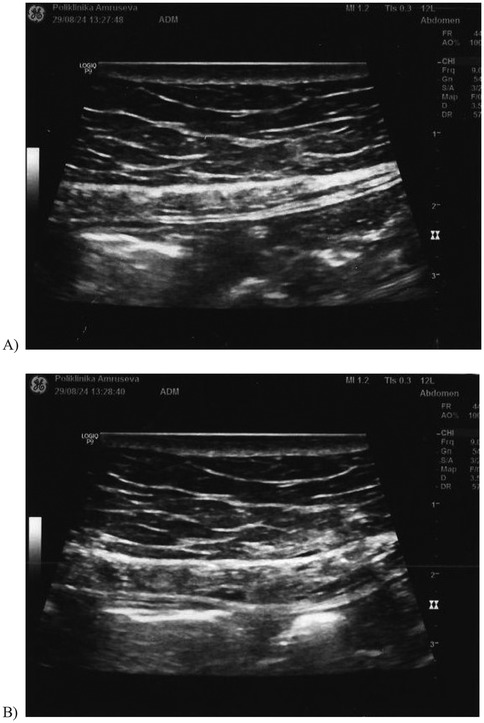

After the set of laboratory tests, colonoscopy, the abdominal ultrasound, and the CT of the abdomen and pelvis, an anesthesiologist examined the patient. This examination took place nearly 2 months after the onset of abdominal pain. The abdomen status was that the abdomen was soft and without tenderness. After an abdominal palpation, the anesthesiologist performed a test for positive or negative Carnett's sign. The test was performed with the patient in a supine position with the arms crossed over the chest. The patient was then asked to raise his head and feet off the table, while the doctor pushed on the painful spot. If the contraction of the abdominal muscles relieved the pain, the source was probably intra-abdominal, and Carnett's sign would be negative. However, if the source of the pain was in the abdominal wall, the contraction of the abdominal muscles would not reduce the pain and may even worsen it; then Carnett's sign is positive, which was the case in this patient. Additionally, during the examination, the patient localized the pain with his finger. With the positive Carnett's sign and localized pain in the abdominal wall, the anesthesiologist suspected the ACNES syndrome, which was consistent with neuropathic pain presented by the skin burning sensation. These two clinical signs indicated a block of the anterior cutaneous nerve followed by ultrasound control. The patient was placed supine, and the site of maximal tenderness of the abdominal wall was marked. This was followed by skin preparation of the abdominal wall with chlorhexidine and octenisept. A 10 mHz linear ultrasound probe was used (Figure 1A). The medial border of the rectus muscle and the linea alba were visualized, and its lateral end forms the linea semilunaris. The nerve was visualized as a hyperechoic line within the rectus muscle.

Figure 1. The ultrasound image of the abdominal wall: (A) before the block of the anterior cutaneous nerve and (B) after the block of the anterior cutaneous nerve.

Under aseptic conditions, 22 G spinal needle was advanced in the longitudinal axis of the probe. It is mandatory to follow the needle tip all the time to avoid penetration of the peritoneum.

Dexamethasone 4 mg/1 mL + 2% lidocaine 2 mL (total volume of 3 mL) was injected while checking for the spread of the hypoechoic zone in the region (Figure 1B).